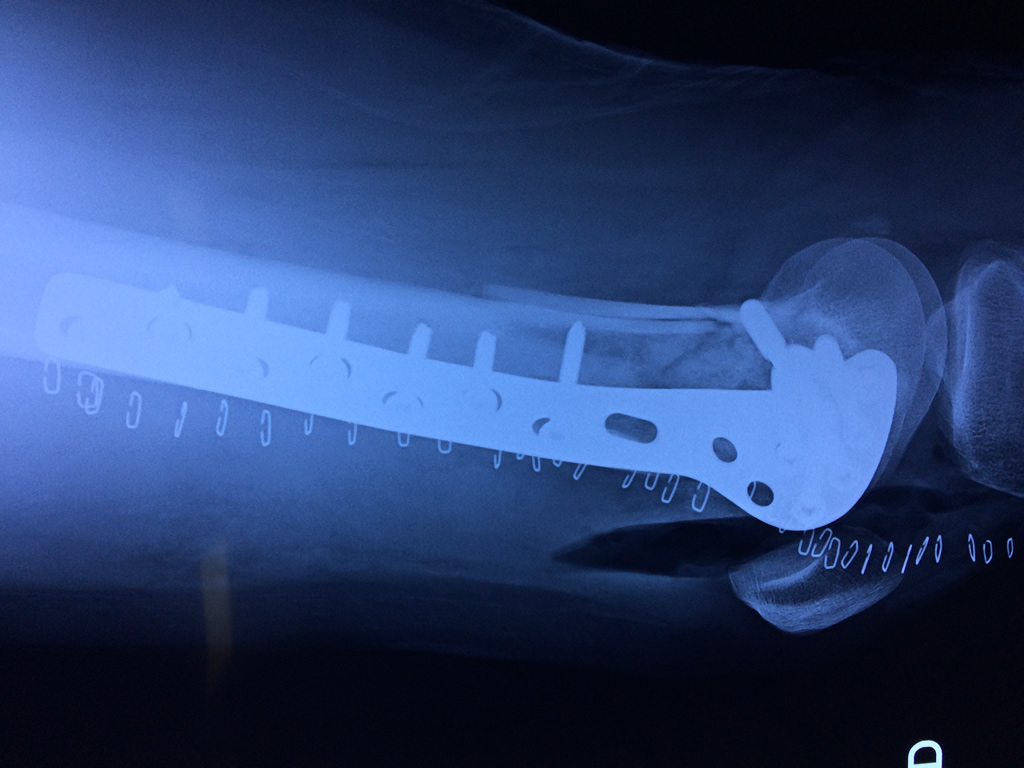

Cirugías de Rodillas

El fémur es el hueso del muslo, el segundo segmento del miembro inferior. Es el hueso más largo, fuerte y voluminoso del cuerpo humano.